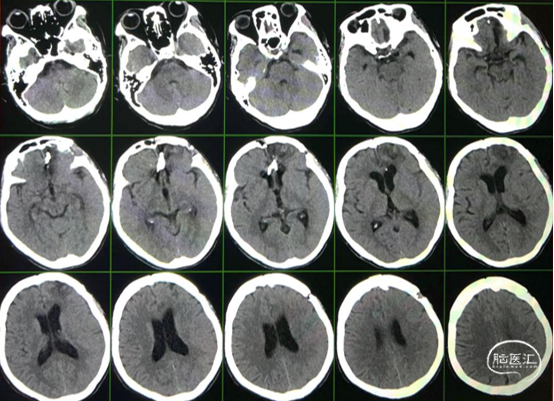

头颅CT

术前

术后第一天

4个月复查,停单抗

8个月复查

停单抗

前

后

1年半复查

术后第一天复查头颅CT